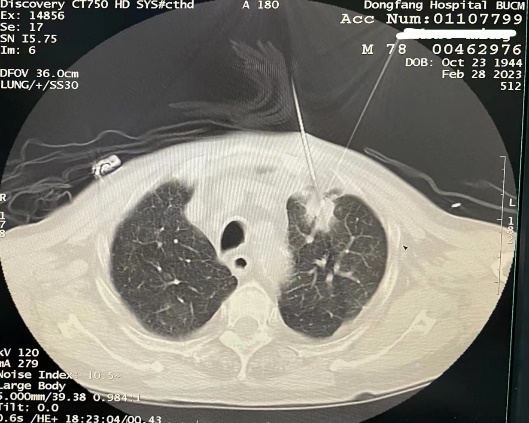

2023年2月28日,通过精心术前准备,北京中医药大学东方医院肿瘤科李泉旺教授带领团队成功实施了首例CT引导下肺癌电冷复合消融术。患者术中全程清醒无痛苦,术中术后生命体征平稳,手术持续30分钟,过程安全有序。

病人仰卧位CT床扫描定位,右肺上叶可见软组织肿块影,局部麻醉后,按照手术设计穿刺路径,分别将冷冻消融针(阴极针)和电解消融针(阳极针)经皮穿刺进入靶病灶,冷冻后CT扫描可见冰球覆盖靶病灶,复温后开启阳极消融针进行电解消融,致冰球完全融化,内部见电解后气泡出现,多种机制导致肿瘤组织坏死,手术共用时30分钟顺利结束。